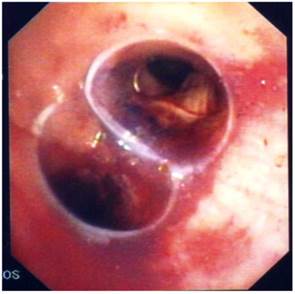

Figure 6

Bifurcated silicone stent.

J Cancer Image

Recent ACCP Lung Cancer Guidelines mention several interventional bronchoscopic modalities for palliation of dyspnea due to inoperable malignant CAO.[28] The results of the present prospective, controlled study confirm the considerable benefit of interventional bronchoscopic management of such patients and make an argument that patients with malignant CAO treated endoscopically have less dyspnea, better QoL, improved physical function and longer survival than patients with oncologic treatment alone. Combined interventional and oncologic treatment should be considered in any multidisciplinary cancer care program and offered to all patients with lung cancer and inoperable CAO, especially when post-obstructive atelectasis is present. Since such an approach is often limited by the lack of interventional equipment and skills, the urgent need for respiratory physicians' training in therapeutic bronchoscopy and development of interventional units is also highlighted.[29] (Figures 3-8) Additional treatment with radiotherapy could be used based on the patient performance status and local interventional prior or after stent placement-debulking.[30-36] Multimodality treatment is necessary for patients with central tumors local treatment should be accompanied with systematic treatment when possible.